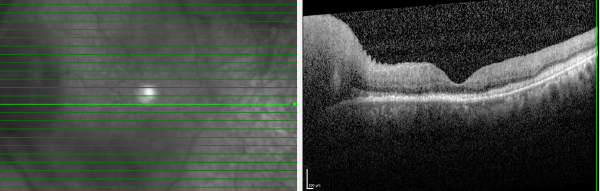

This case report discusses a patient with a history of DLBCL who presented with progressive optic neuropathy despite negative neuro-imaging and cerebrospinal fluid analysis. The case illustrates the limitations of standard CNS surveillance in detecting occult infiltration and highlights the necessity of tissue biopsy for definitive diagnosis.